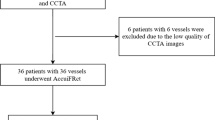

The present study surveyed the title and abstracts of 384 articles. The full text of 107 articles was carefully examined, and eighty-two articles were excluded for reasons such as lack of full text, use of methods other than AI, conference articles, articles other than English, and articles with unclear results, and twenty-five articles were included in the study (Fig. 1).